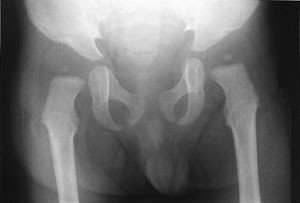

Omfattende radiologisk utredning ble rekvirert. Røntgen av kraniet viste et relativt stort nevrokranium (fig 2) med sannsynlig fortykket calvarium i basale deler. Røntgen av columna viste en kyfotisk knekk på torakolumbalovergangen (fig 3). Røntgen av bekken viste dysplastiske hofter bilateralt (fig 4). Røntgen av håndledd viste forandring av metakarpene. Røntgenologenes endelige konklusjon var dysostosis multiplex, forenlig med Hurlers syndrom. Undersøkelse hos øyelege styrket denne mistanken ytterligere, da det ble funnet bilateral, diffus tilsløring av hornhinnene. Plastisk kirurg bekreftet at det forelå triggerfinger på høyre hånds 4. finger, et typisk funn ved Hurlers syndrom.